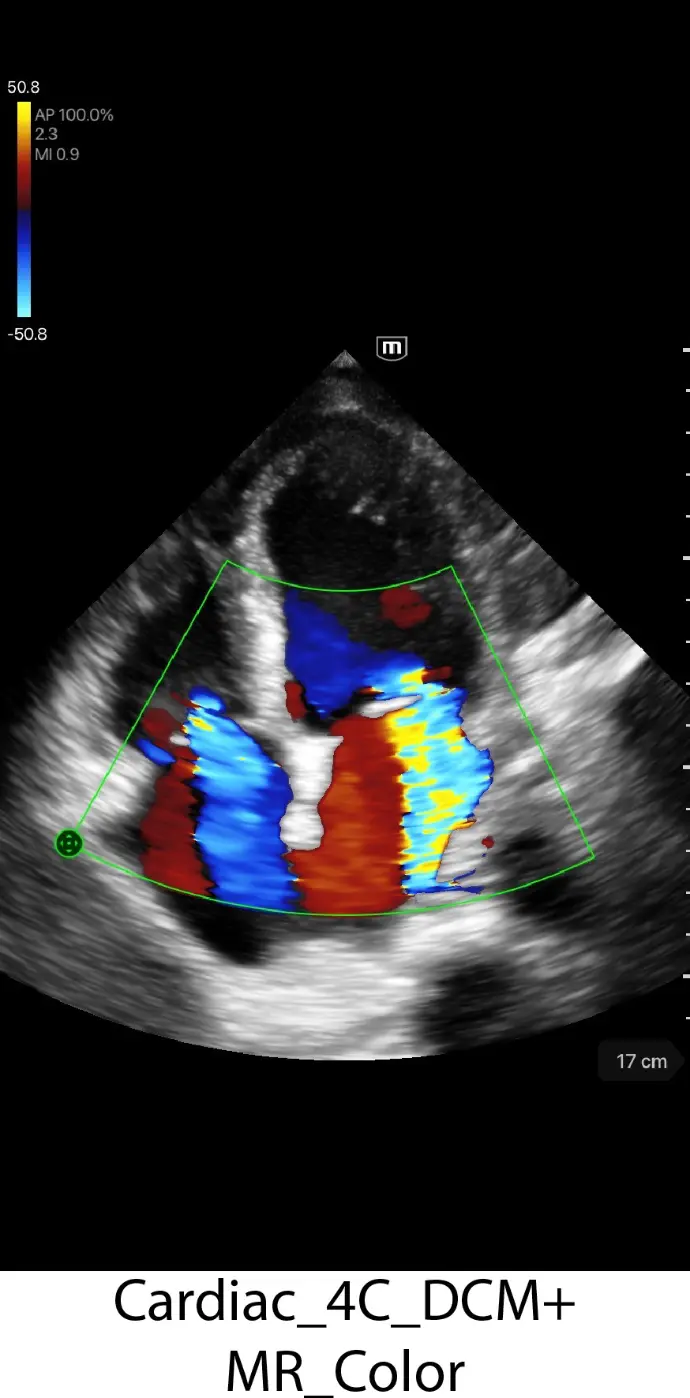

Клинични снимки